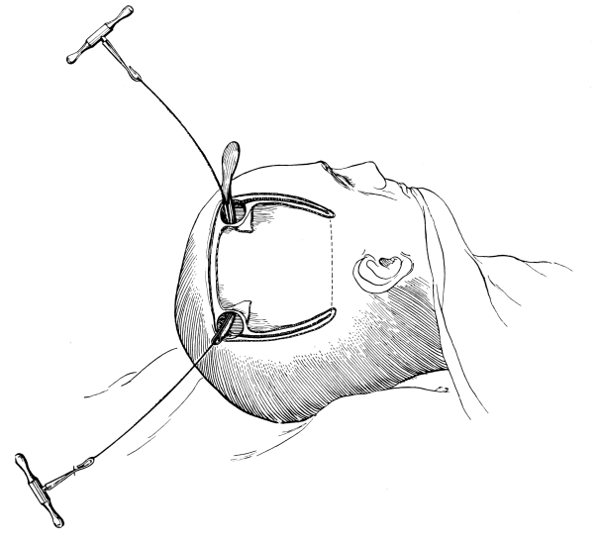

Craniotomy, or osteoplastic resection of the skull, was first carried out by Wagner. It is proposed to describe that method only which, by experience, has been found to meet all requirements—the formation of the osteoplastic flap by means of the hand-trephine, Gigli’s saw, and de Vilbiss’s forceps.

The protective gauze dressing and scalp-tourniquet are applied

as before. A large ![]() -shaped

incision is made in such a manner as

to include the area which it is desired to expose. The two vertical

limbs of the incision should converge to such a degree as to allow of

the subsequent ready fracture of the flap along its base. The knife

is entered at one extremity, carried down to the bone, and the three

incisions rapidly made, one after the other. Along the line of each

of the three incisions, the pericranium is stripped away from the bone

so as to allow of adequate exposure. At the anterior and posterior

angles of the flap the tissues are retracted a little more, permitting

the application of a half-inch diameter trephine. Here the two

trephine-holes are bored—with the usual precautions against damage

to the dura mater—and the two disks of bone elevated and removed.

-shaped

incision is made in such a manner as

to include the area which it is desired to expose. The two vertical

limbs of the incision should converge to such a degree as to allow of

the subsequent ready fracture of the flap along its base. The knife

is entered at one extremity, carried down to the bone, and the three

incisions rapidly made, one after the other. Along the line of each

of the three incisions, the pericranium is stripped away from the bone

so as to allow of adequate exposure. At the anterior and posterior

angles of the flap the tissues are retracted a little more, permitting

the application of a half-inch diameter trephine. Here the two

trephine-holes are bored—with the usual precautions against damage

to the dura mater—and the two disks of bone elevated and removed.

Between these two trephine-holes the dura mater is separated from the bone and the special director introduced, entering at the one hole, emerging at the other, and lying throughout between the dura and the bone. The saw is now passed along the groove of the director, the handles affixed, and the bone intervening between the two trephine-holes divided, not straight out to the surface, but bevelled or cut in such an oblique manner that the bone-flap, when replaced, rests on a ledge (see Figs. 17-19). The sawing process[26] generates considerable heat, and the assistant should be instructed to keep up irrigation with saline solution or sterilized water. The sawing is carried out by steady side-to-side traction, without jerks; if the saw breaks, the special handle may be attached, thus obviating the necessity of introducing a new saw.

Fig. 17. First Stage in the Formation of an Osteoplastic Flap. Gigli’s saw, protected from the dura mater by the special director, passing between the two trephine-holes. For further description, see text.